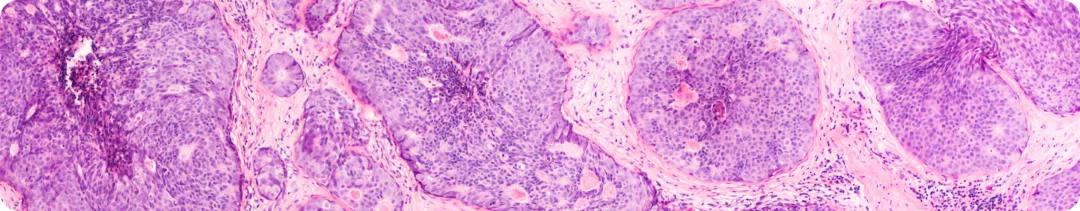

Результаты анализа диспропорциональности

Согласно результатам анализа, применение препаратов эндокринной терапии, а именно анастрозола, летрозола, эксеместана, тамоксифена и фулвестранта, ассоциировалось со значимо более высокой частотой сообщений о нейрокогнитивных нарушениях. При этом наибольшая ассоциация была характерна для анастрозола (сообщаемое отношение шансов (сОШ) 1,52, 95% доверительный интервал (ДИ) 1,37–1,67).

Для ингибиторов CDK4/6 такая ассоциация была обнаружена только для палбоциклиба (сОШ 1,41, 95% ДИ 1,34–1,48), тогда как применение абемациклиба и рибоциклиба не было связано с нейрокогнитивными нарушениями.

Обнаруженные нейрокогнитивные нарушения в основном были связаны с обучением и памятью, а также с языковыми способностями. В частности, применение палбоциклиба было связано с нарушениями памяти и обучения, а также с языковыми нарушениями.